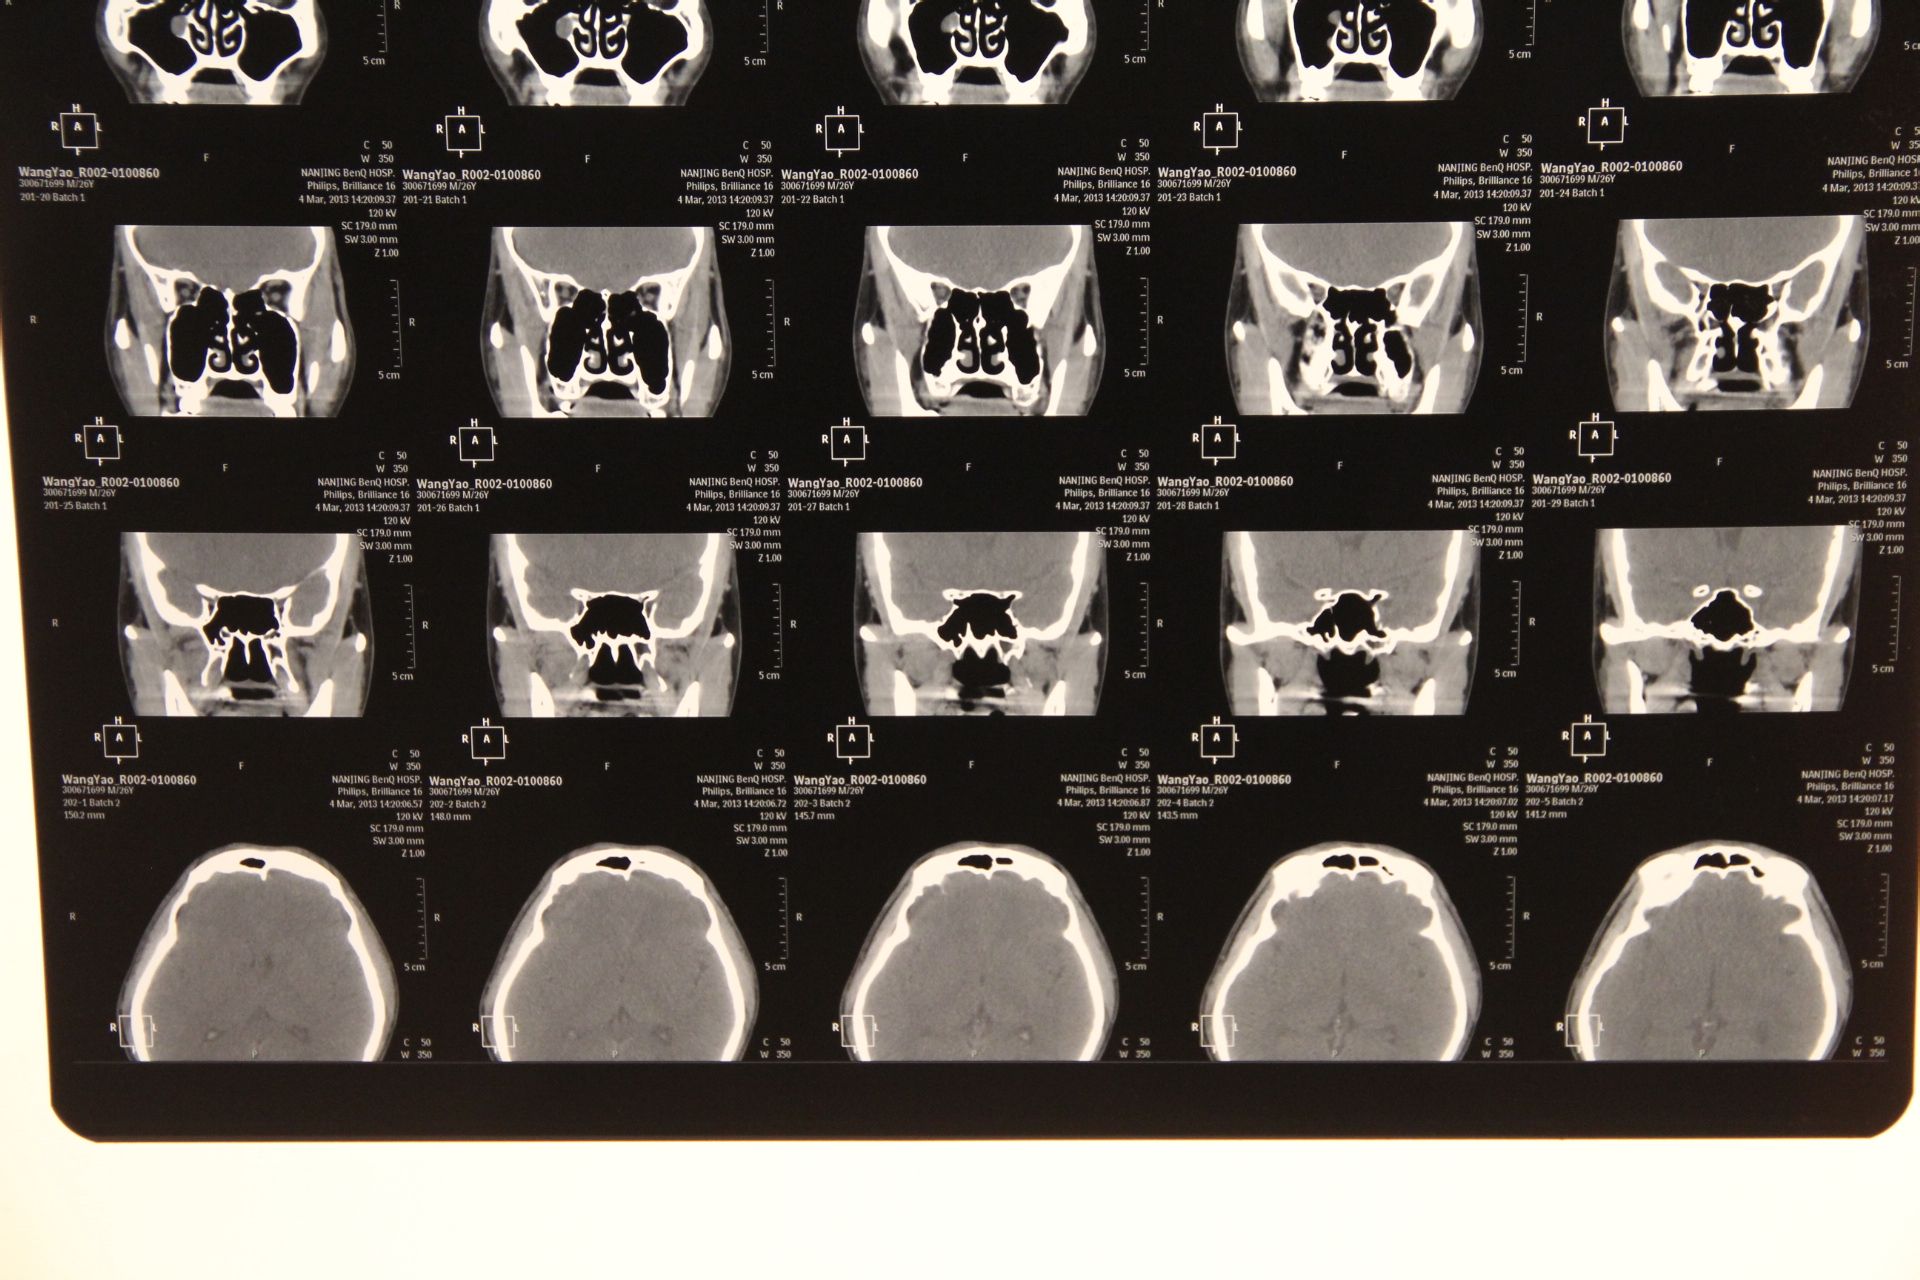

帮我看下这个ct图片,上颌窦里面有东西.现在鼻子很不舒服.

ct上颌窦内稍高密度影是软组织还是液体呢

右上颌窦炎